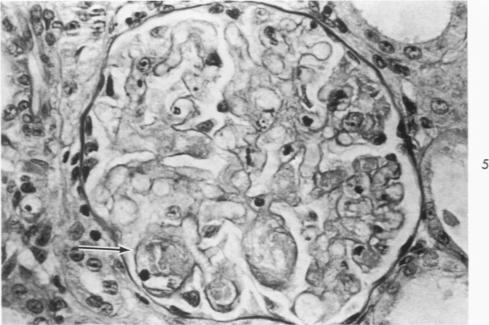

The acute unmodified rejection of (Lewis x Brown Norway) F(1) to Lewis renal allografts is characterized by an early and progressive lymphoid cell infiltrate, glomerular necrosis, necrotizing arteritis and ischemic cortical necrosis leading to graft destruction. A single low dose of enhancing antiserum given at the time of transplantation prolongs graft survival by abrogating the necrotizing lesions in glomeruli and arteries and the subsequent cortical necrosis. Passive enhancement in this model is interpreted as representing predominantly a block in the humoral antibody-mediated rejection response. It is suggested that the block is effected mainly, peripherally, ie, at the level of the transplanted kidney itself.

(Lewis×Brown Norway)F1 对 Lewis 肾移植的急性未修饰排斥反应的特征是早期进行性淋巴细胞浸润、肾小球坏死、坏死性动脉炎和缺血性皮质坏死,最终导致移植物破坏。移植时给予单次低剂量增强抗血清可通过消除肾小球和动脉中的坏死性病变以及随后的皮质坏死来延长移植物存活时间。该模型中的被动增强主要被解释为体液抗体介导的排斥反应受阻。有人提出,这种阻断主要在周围起作用,即在移植肾本身的水平上。